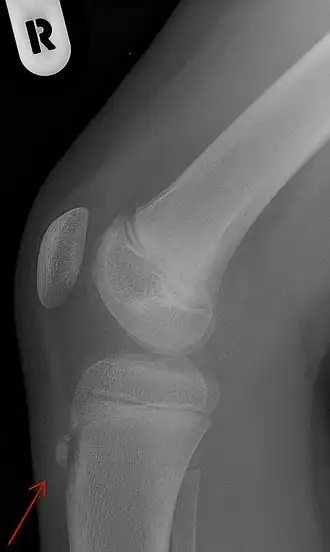

Zijdelingse röntgenfoto van een knie met de ziekte van Osgood-Schlatter

De ziekte van Osgood-Schlatter[4][2] is een ziekte waarbij er pijn optreedt op de plaats van de aanhechting van de kniepees aan het scheenbeen. Hierbij ontstaat er een zeer gevoelige bobbel op het scheenbeen net onder de knie. De ziekte is voor het eerst beschreven door de Amerikaanse chirurg Robert Osgood en de Zwitserse chirurg Carl Schlatter, onafhankelijk van elkaar in 1903.[5][6]